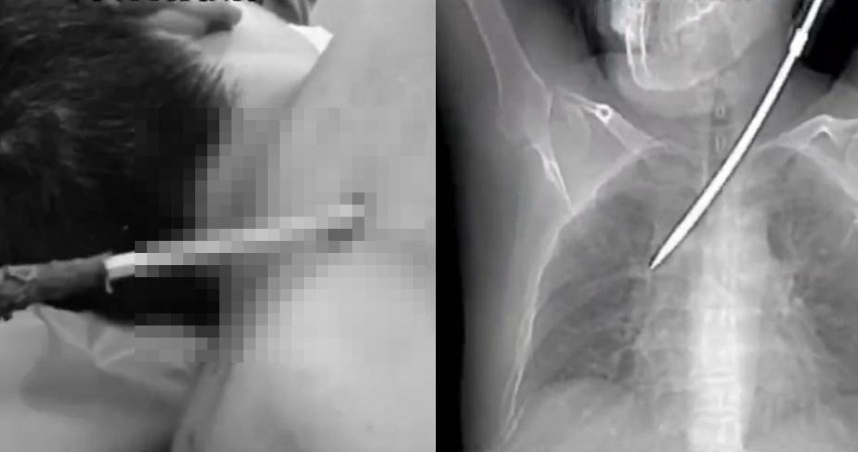

大陸廣東26日驚傳一起驚悚事故,一名44歲男電梯工人蹲下作業,卻遭一把從高空墜落約有30公分長的螺絲起斯插進胸膛,所幸送醫救治後已脫離生命危險。(圖/翻攝自微博)

禍從天降!近日大陸廣東一名44歲男電梯工人蹲在路邊工作時,突然遭一把從20多公尺高掉落的大螺絲起子,從背後插進胸腔,命懸一線;在緊急送醫後,火速動手術取出,醫師也呼籲民眾發生胸外傷有異物扎入的狀況,請勿自行拔除,應及早就醫。

根據陸媒《羊城晚報》報導,廣東一名44歲男電梯工人26日上午9時許,蹲在路邊埋首工作,沒想到在他頭上20多公尺處有一把長約30公分的螺絲起子掉下來,不偏不倚從他的背後插進胸槍,畫面十分驚悚。

與受傷工人一起工作的同仁立刻報案,叫來救護車將他送往廣東藥科大學附屬第一醫院急診,工人當日就接受手術搶救,所幸醫師將插入他胸腔的螺絲起子完整取出,他已經脫離生命危險,手術隔日工人就能下床活動,逃過一劫。醫師也提醒其他民眾,發生胸外傷且有異物扎入身體,切記不要自行拔除,必須及時就醫讓專業的醫護人員處理。